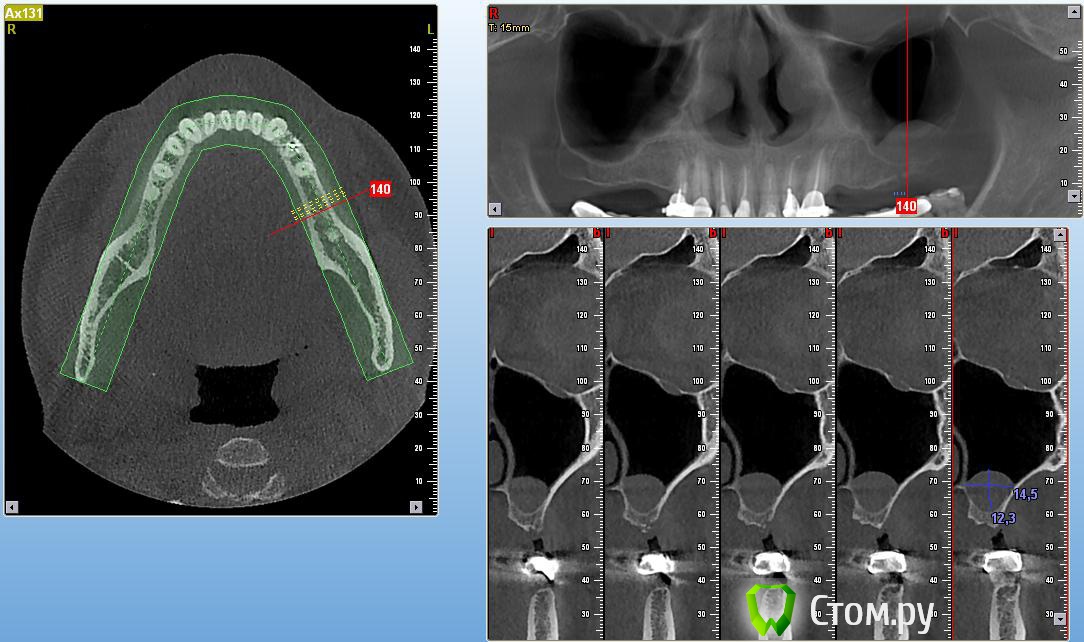

Тимур86 Опубликовано 28 ноября, 2013 Поделиться Опубликовано 28 ноября, 2013 пациент молодой человек,не курит,гаймориты не беспокоят!какова тактика? Ссылка на комментарий

DoktorDre Опубликовано 28 ноября, 2013 Поделиться Опубликовано 28 ноября, 2013 кажется, это мукоцеле. тактика-делать синус, если будет мешать отслойке, попробывать аспирировать секрет шприцом. Ссылка на комментарий

Doctorstomlis Опубликовано 29 ноября, 2013 Поделиться Опубликовано 29 ноября, 2013 Здравствуйте!У меня что-то подобное.Как Вы думаете,какова здесь тактика(я имею ввиду патологию в гайморовой пазухе) Ссылка на комментарий

ВИТА Опубликовано 31 января, 2014 Поделиться Опубликовано 31 января, 2014 Здравствуйте!У меня что-то подобное.Как Вы думаете,какова здесь тактика(я имею ввиду патологию в гайморовой пазухе)я бы сделала откр синус лифт аккуратно....по видимому это гипертрофия слизистой, подниматься даже лучше будет из-за своей плотности Ссылка на комментарий